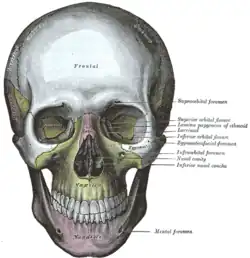

Fossa infratemporal esquerda. O crânio da frente.

O crânio da frente. Seção horizontal das cavidades nasais e orbitárias.